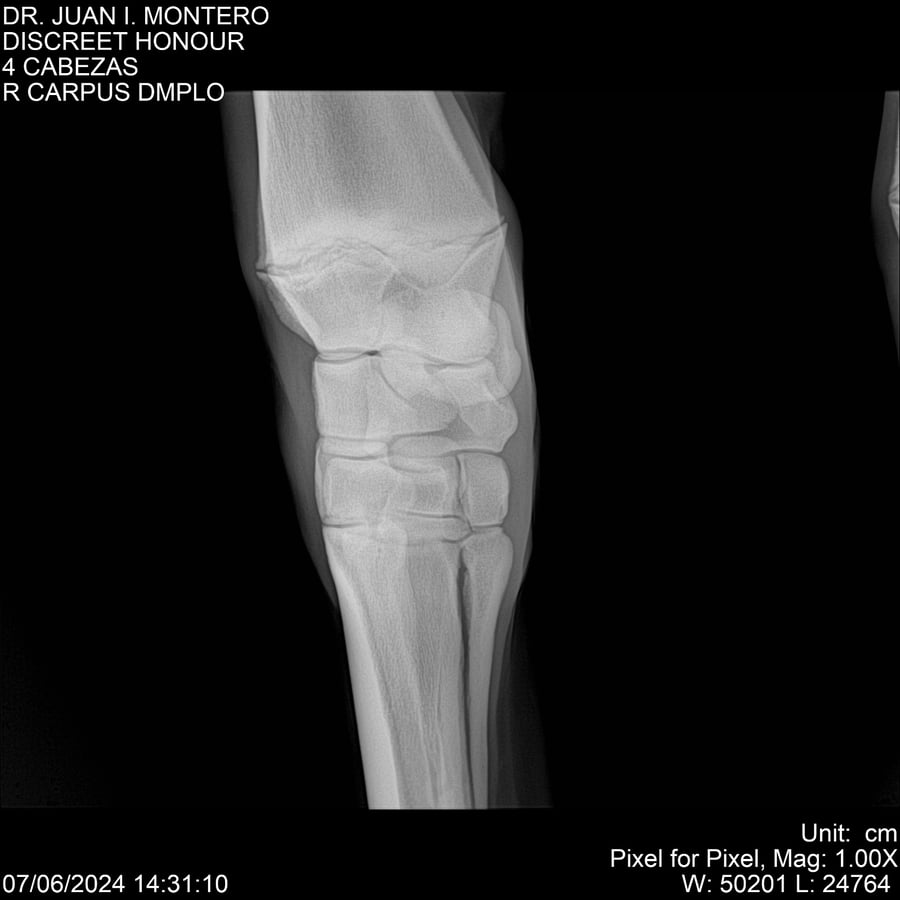

LOTE 6, DISCREET HONOUR 🔥 🔥 🔥 Lote Anterior Volver al remate Lote Siguiente Ficha Contacto Montevideo - Ficha del Lote Identificador: #281093 Categoría: Yeguarizos Montevideo - 82 Visualizaciones ClicData Contacto Empresa: Abelenda N. R., Walter Hugo Nombre*: Teléfono* : E-mail* : Mensaje Enviar Registrese gratis Este contenido Exclusivo está disponible sólo para usuarios registrados Ingresar